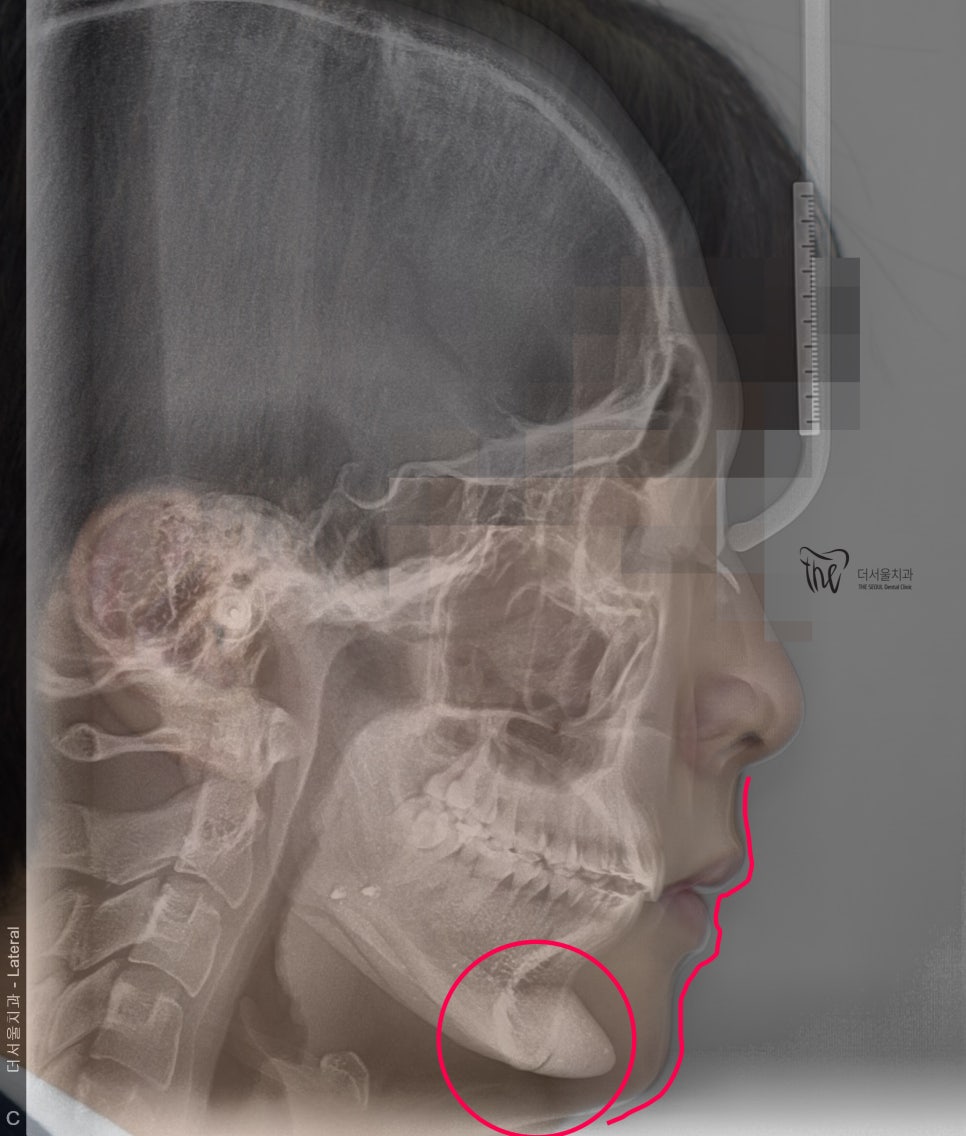

측면 두부방사선 사진 및 안모의 측면사진의

중첩 된 결과입니다.

사진을 보면, 턱이 거의 없는 무턱 증세를 띄고

있는 것이 한 눈에 보여집니다.

그리고, 정면 및 측면에서 본 모습으로는

살짝 개방교합(Open bite)의 형태를 보여줍니다.

측면 두부방사선, 중첩 사진에 따른

전후 사진을 한번에 보여드립니다.